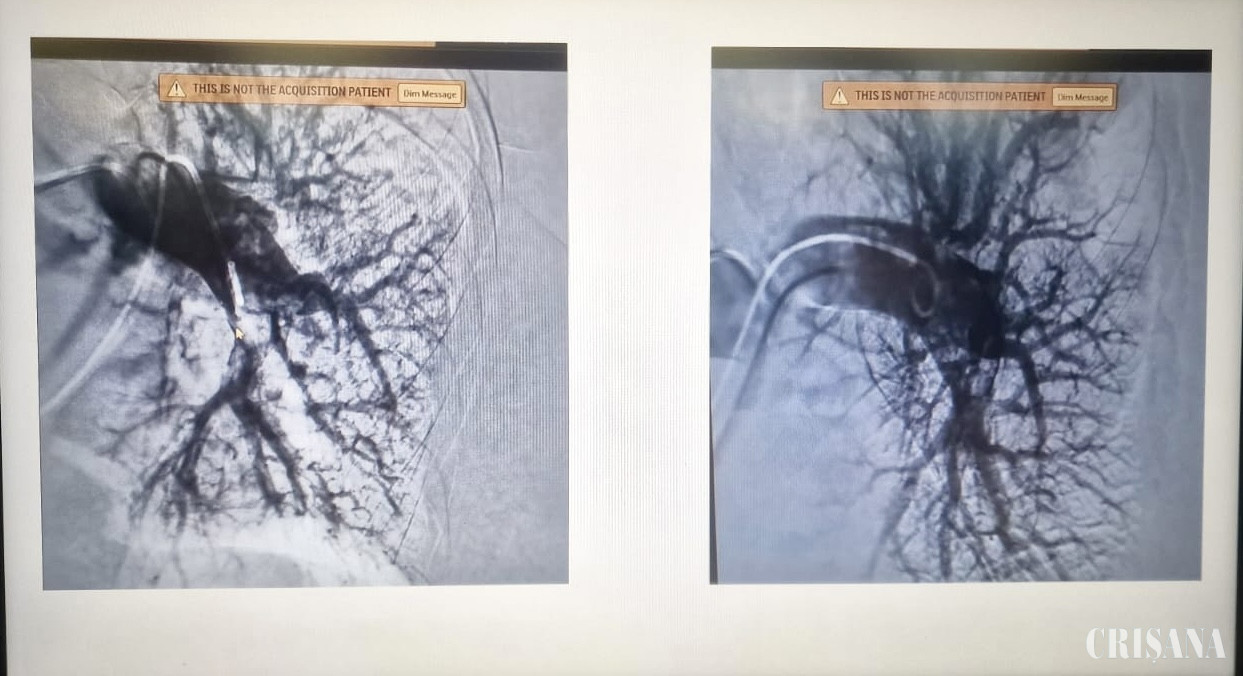

Pe 16 ianuarie 2025, în premieră națională, s-a efectuat trombectomia pe cateter la nivelul arterelor pulmonare. Intervenția a presupus introducerea unui cateter la nivelul arterelor pulmonare și aspirarea conținutului trombotic, restabilind astfel permeabilitatea și fluxul de sânge dinspre cord înspre plămân. Intervenția a decurs bine, pacientul a avut o evoluție favorabilă și este externat.

În acest caz însă, din cauza AVC-ului recent și al intervențiilor chirurgicale, pacientul avea contraindicații absolute pentru tromboliză. Astfel, în cadrul unei comisii multidisciplinare compusă din medicii cardiologi intervenționiști, radiologi intervenționiști și anesteziști, s-a decis efectuarea unei trombectomii pe cateter cu ajutorul unui dispozitiv de aspirație (penumbra) care permite aspirarea selectivă a cheagului, limitând pierderile de sânge. Trombectomia pe cateter este o procedură minim invazivă utilizată pentru a elimina cheagurile de sânge (trombi) din vase, în special în cazurile de tromboembolism pulmonar sau de accident vascular cerebral ischemic.